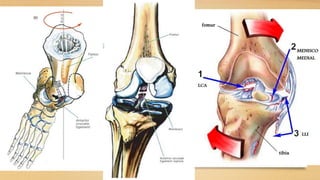

Meniscos se desplazan hacia

posterior en la flexion, en la

extensión están en su sitio

Durante la extensión, el

compartimento externo es el

primero en alcanzar la extensión

completa, al ser la extensión

completa se da un mecanismo de

rosca al rotar internamente el femur

sobre la tibia, bloqueando la rodilla